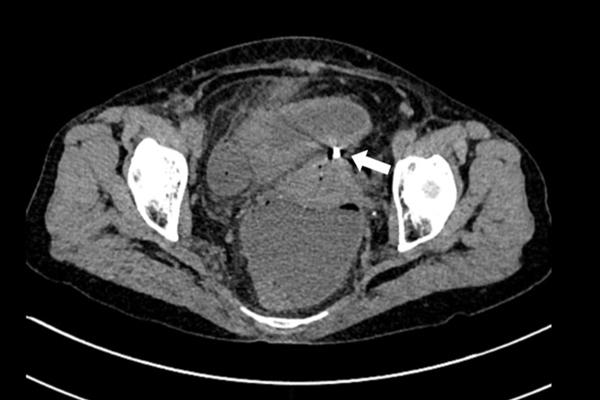

Hình ảnh chụp cho thấy dụng cụ tử cung xuyên qua thành tử cung vào ruột. Ảnh: Bệnh viện cung cấp

Khi vào viện, bệnh nhân có biểu hiện viêm phúc mạc như bụng chướng, ấn đau khắp bụng. Chụp cắt lớp vi tính thấy hình ảnh dịch khí tự do trong ổ bụng, tắc ruột cơ năng, dày thành ruột vị trí hố chậu phải và dị vật xuyên thủng đáy tử cung.